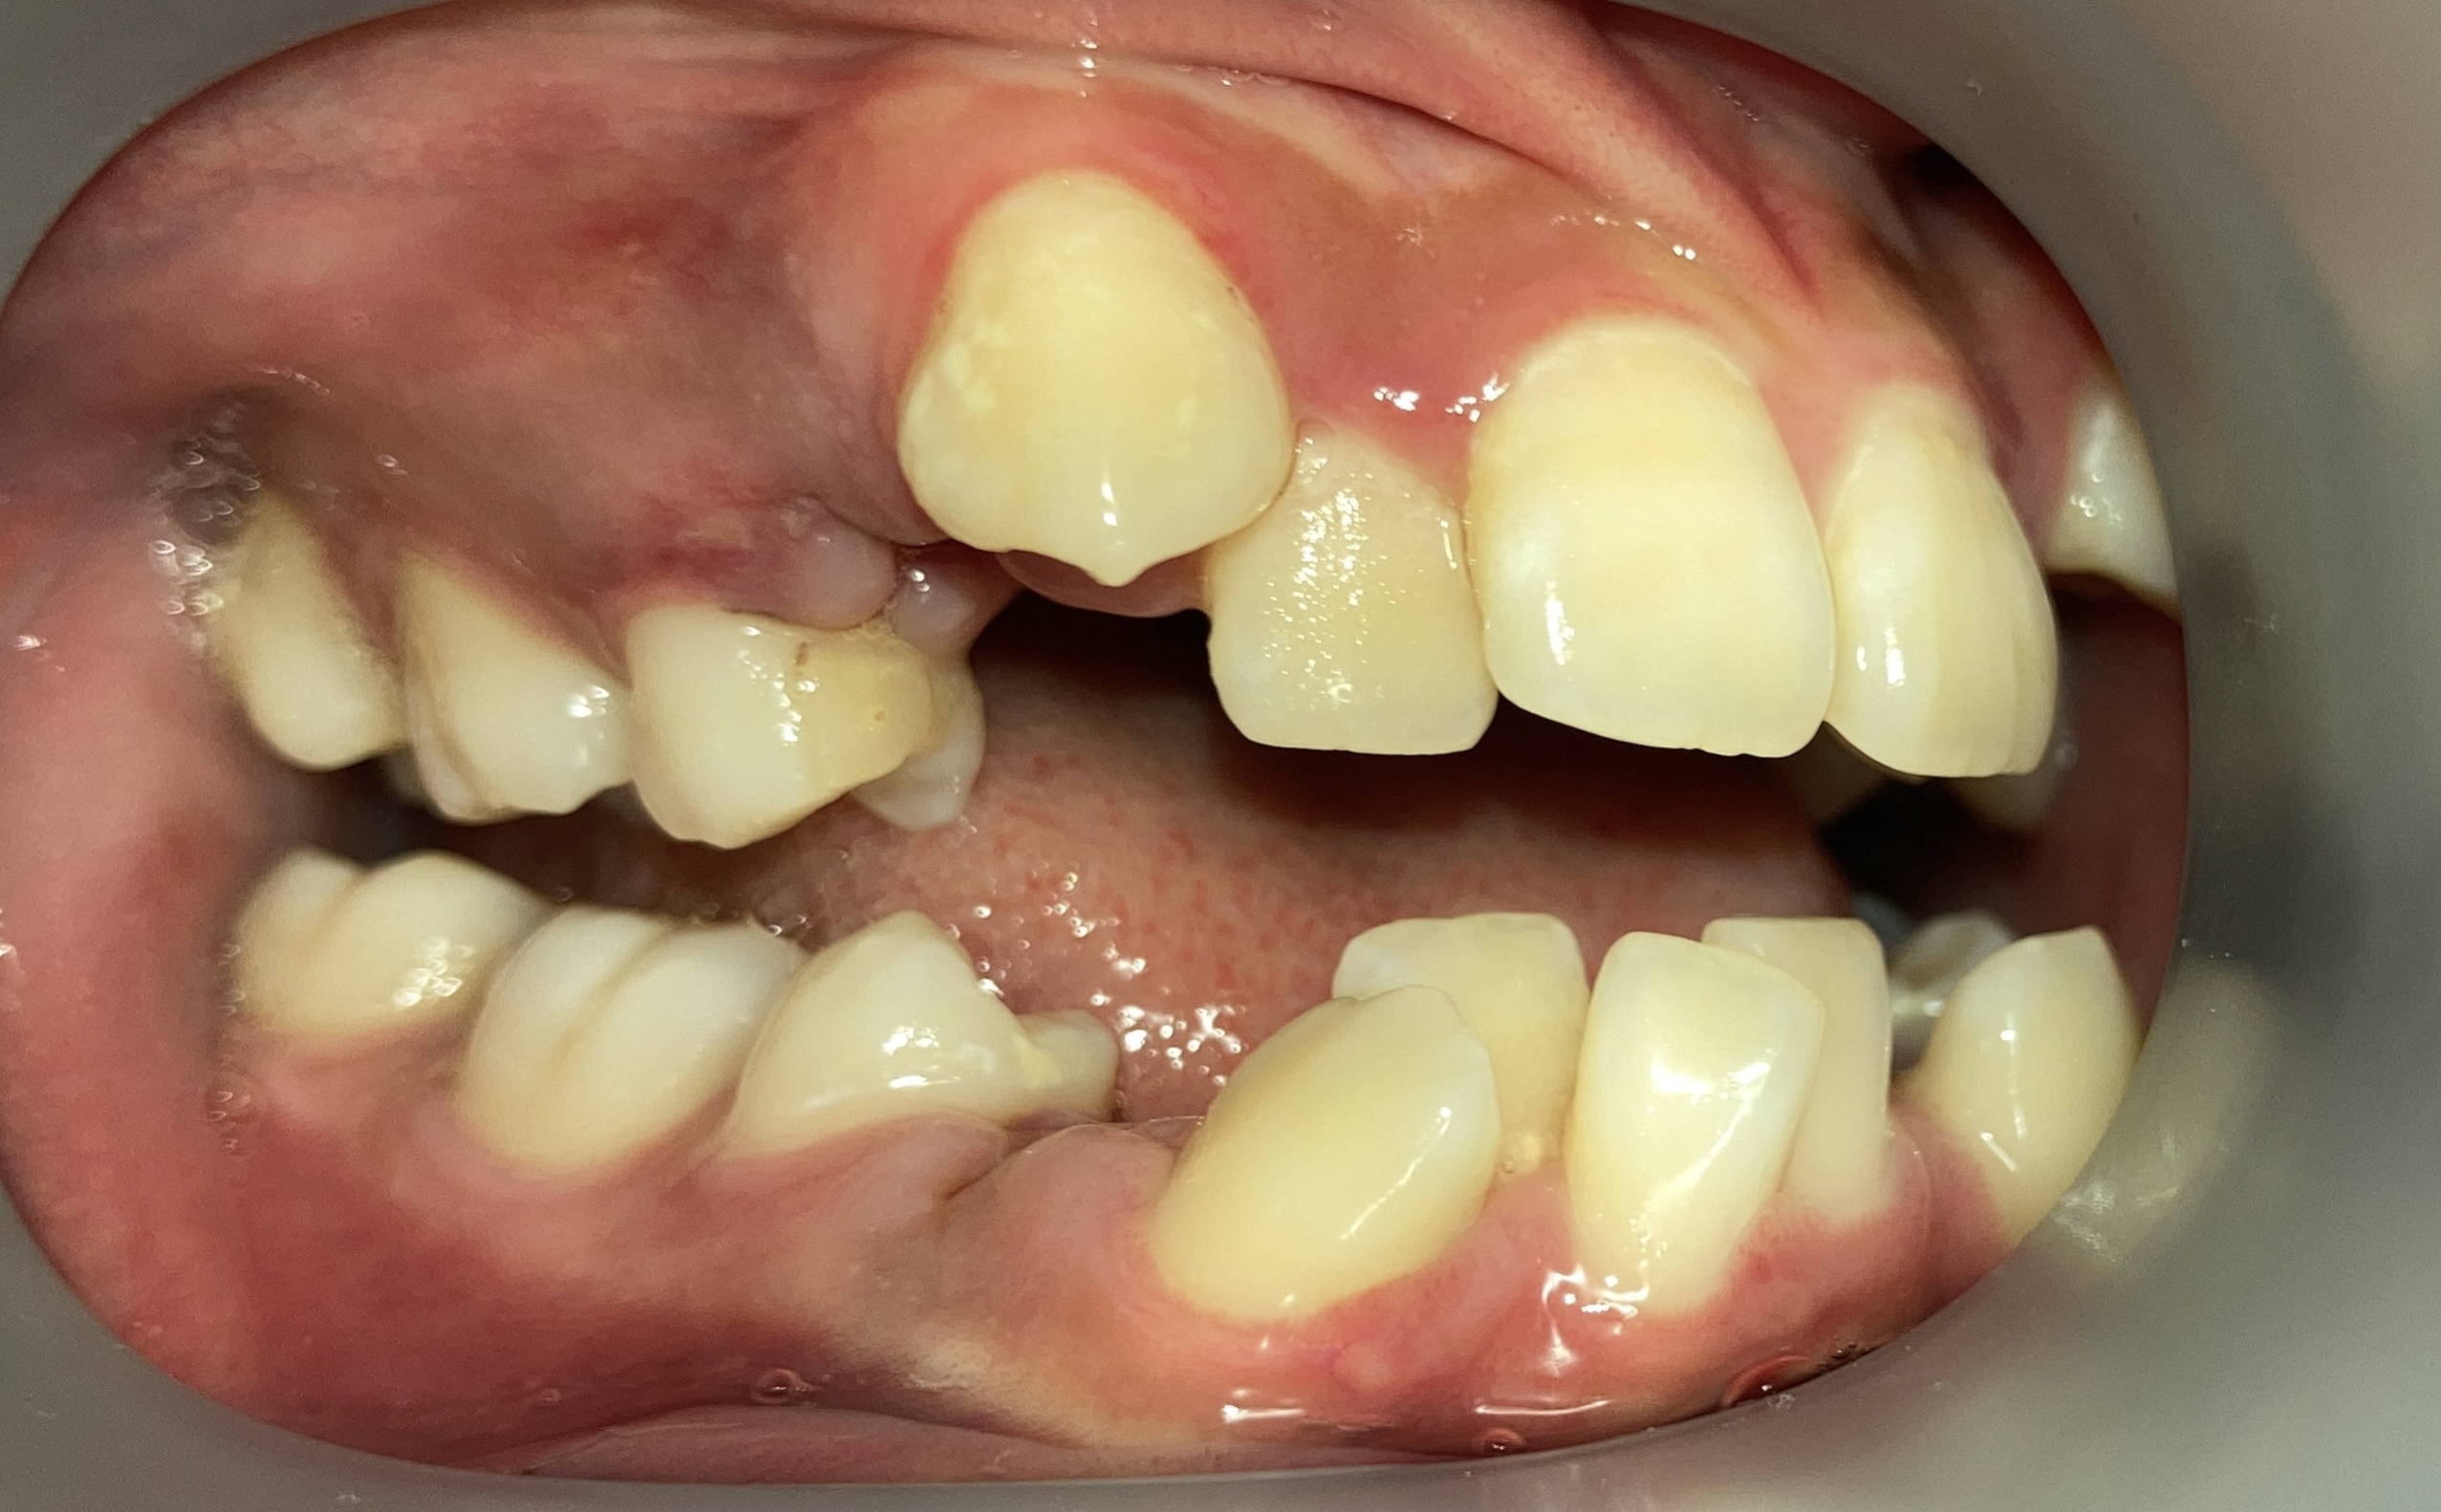

他院の非抜歯矯正後、当院で再治療したケース

リカバリー症例の初診時|口元の突出|奈良の矯正歯科

初診時

リカバリー症例の初診時の口腔内|奈良の矯正歯科

他院で非抜歯矯正を受け、歯並びは改善したものの、口元の突出感が残ったまま治療が終了。当院で精密検査を行った結果、上下4本の抜歯によるリカバリー治療が必要と判断しました。